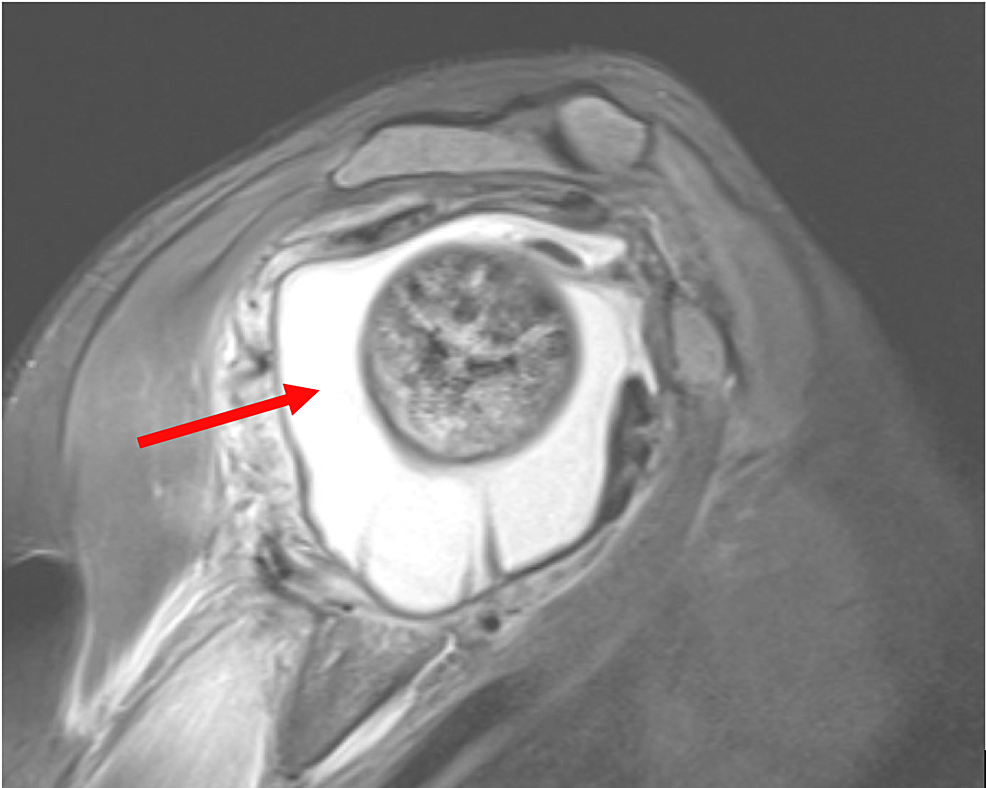

関節炎は通常、X線検査によって診断され、症状がしばらく続いた後にのみ診断されることに注意してください。

ただし、MRI ではさらに多くの情報が得られるため、通常の X 線検査結果の後でも痛みが続く場合は、MRI をリクエストできます。